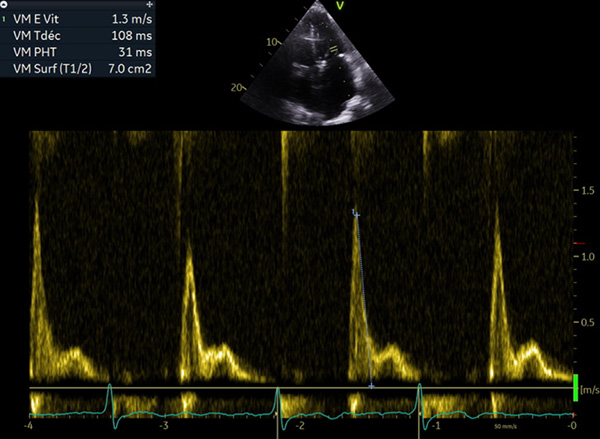

Figure 2 : profil restrictif, onde L

- Phénotype typique : petite cavité VG, hypertrophie modérée, dilatation OG sévère, profil mitral, VCI dilatée